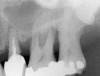

The 2-mm twist drill is used to create an osteotomy 1 mm short of the subantral floor. If any resistance is detected prior to reaching the 3-mm depth, drill penetration must be stopped, because the subantral cortical bone has possibly been reached. Any uncontrolled "push" would penetrate the bone and likely perforate the sinus membrane. A guide pin is then inserted and a radiograph taken to determine if drill penetration has terminated within 1 mm of the subantral floor (Figure 2). If the radiograph indicates that more than 1 mm of bone is present subantrally, the twist drill is used again to penetrate within 1 mm of the sinus floor. Alternately, an osteotomy tip for a piezosurgery unit can be used for this purpose. The final depth of penetration should be verified with another periapical film.

Figure 2  After drilling to a depth of 3 mm with a 2.1-mm twist drill, the guide pin was placed and a radiograph was taken to ascertain if the drill stopped within 1 mm of the subantral floor.

Figure 2